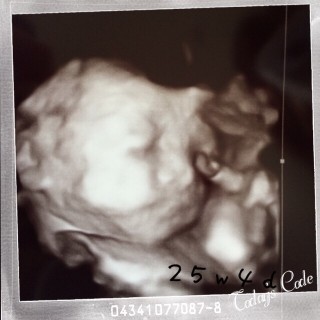

妊娠7ヶ月の終わり頃、妊娠27週くらいになると赤ちゃんが生存するための機能はほぼそろってきます。仮に早産しても生存できる可能性が高くなります。